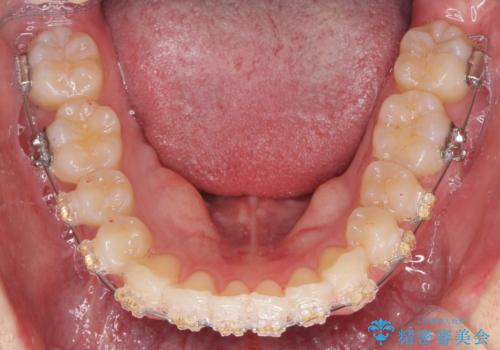

- ワイヤー

- 10ヶ月

- 取り外しの必要なマウスピース矯正ではなくワイヤー矯正を希望され来院されました。

マウスピース矯正、ワイヤー矯正どちらの方法でも治療は可能ですが、ご要望の通りワイヤー矯正で歯の排列を行っていきます。